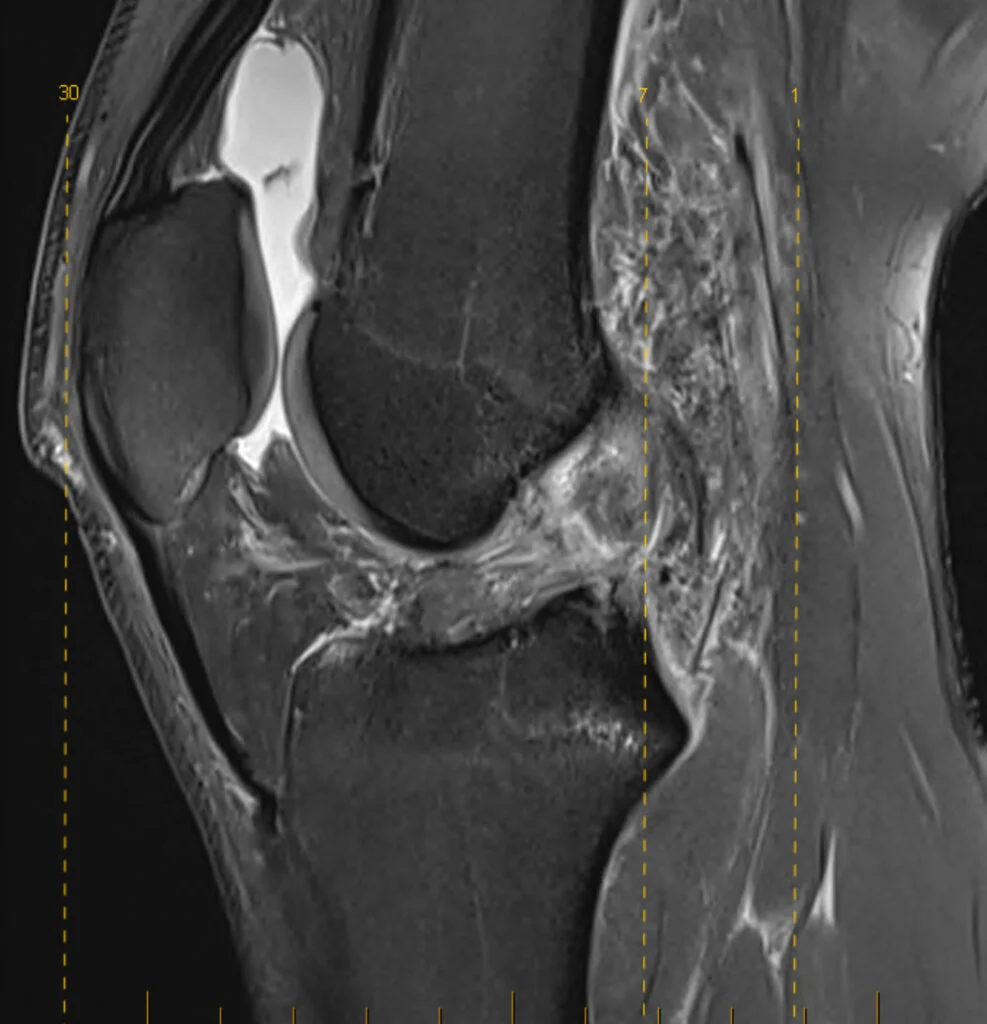

Diagnosing an ACL tear

Dr Awwad will begin with a detailed history and physical examination to assess your knee stability, swelling, and range of motion. Specific clinical tests such as the Lachman test and pivot shift test help assess the integrity of the ACL.

Imaging may include:

A prompt and accurate diagnosis helps determine whether non-surgical or surgical treatment is most appropriate.